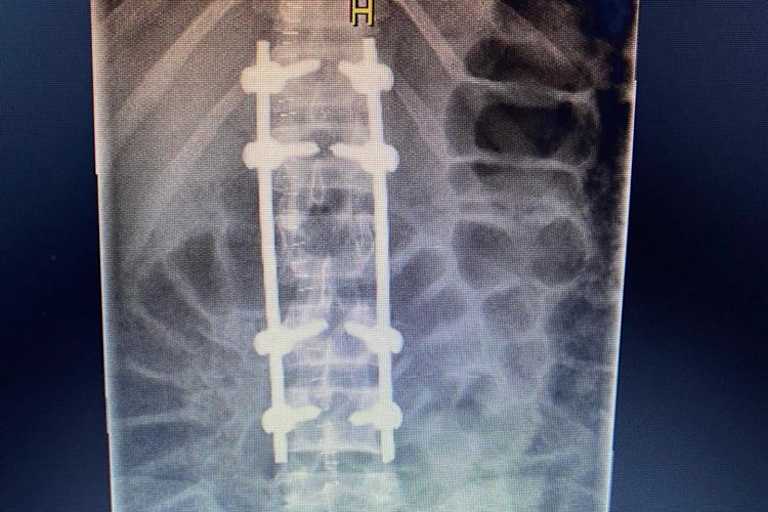

Zur Vorbereitung auf sein WM-Debüt trainierte der Kawasaki-Pilot in Spanien, unter anderem Motocross. Dabei kam es am 16. Februar zu einem schlimmen Unfall, bei dem er sich den Wirbelkörper L1 brach und ausrenkte. Weil große Sorge auf eine Verletzung des Rückenmarks bestand, wurde Currie in Barcelona operiert. Zur Stabilisierung wurden insgesamt fünf Wirbel miteinander verbunden. Glücklicherweise hat Currie volles Gefühl in den Beinen und denkt bereits an seine Karriere. "Ich wurde in einem instabilen Zustand ins Krankenhaus von Barcelona eingeliefert. Glücklicherweise hatte ich jedoch ein volles Gefühl in meinen unteren Gliedmaßen", schilderte der Deutsch-Australier. "Am folgenden Dienstag wurde ich von einem wirklich erfahrenen Team operiert, um den Bruch zu stabilisieren. Alles verlief zu 100 Prozent nach Plan und das OP-Team war sehr zufrieden mit den Ergebnissen und mir wurde gesagt, dass ich am nächsten Tag aufstehen kann. Leider war ich zu schwach und brach zusammen. Das war eine Folge der langen Narkose und weil ich während der OP viel Blut verloren hatte." "Seitdem geht es bergauf und ich baue Schritt für Schritt meine Fitness wieder auf. Ich bin super motiviert und versuche für den Saisonstart in Aragón fit genug zu sein, aber ich kann nicht sicher sagen, ob das tatsächlich passieren wird", ergänzte Currie. "Ich danke allen, die sich in einer der schwierigsten Zeiten meines Lebens um mich gekümmert haben. Ich bin ein großer Glückspilz, aber mein Problem ist angesichts der tragischen Ereignisse, die derzeit auf der Welt passieren, unbedeutend."